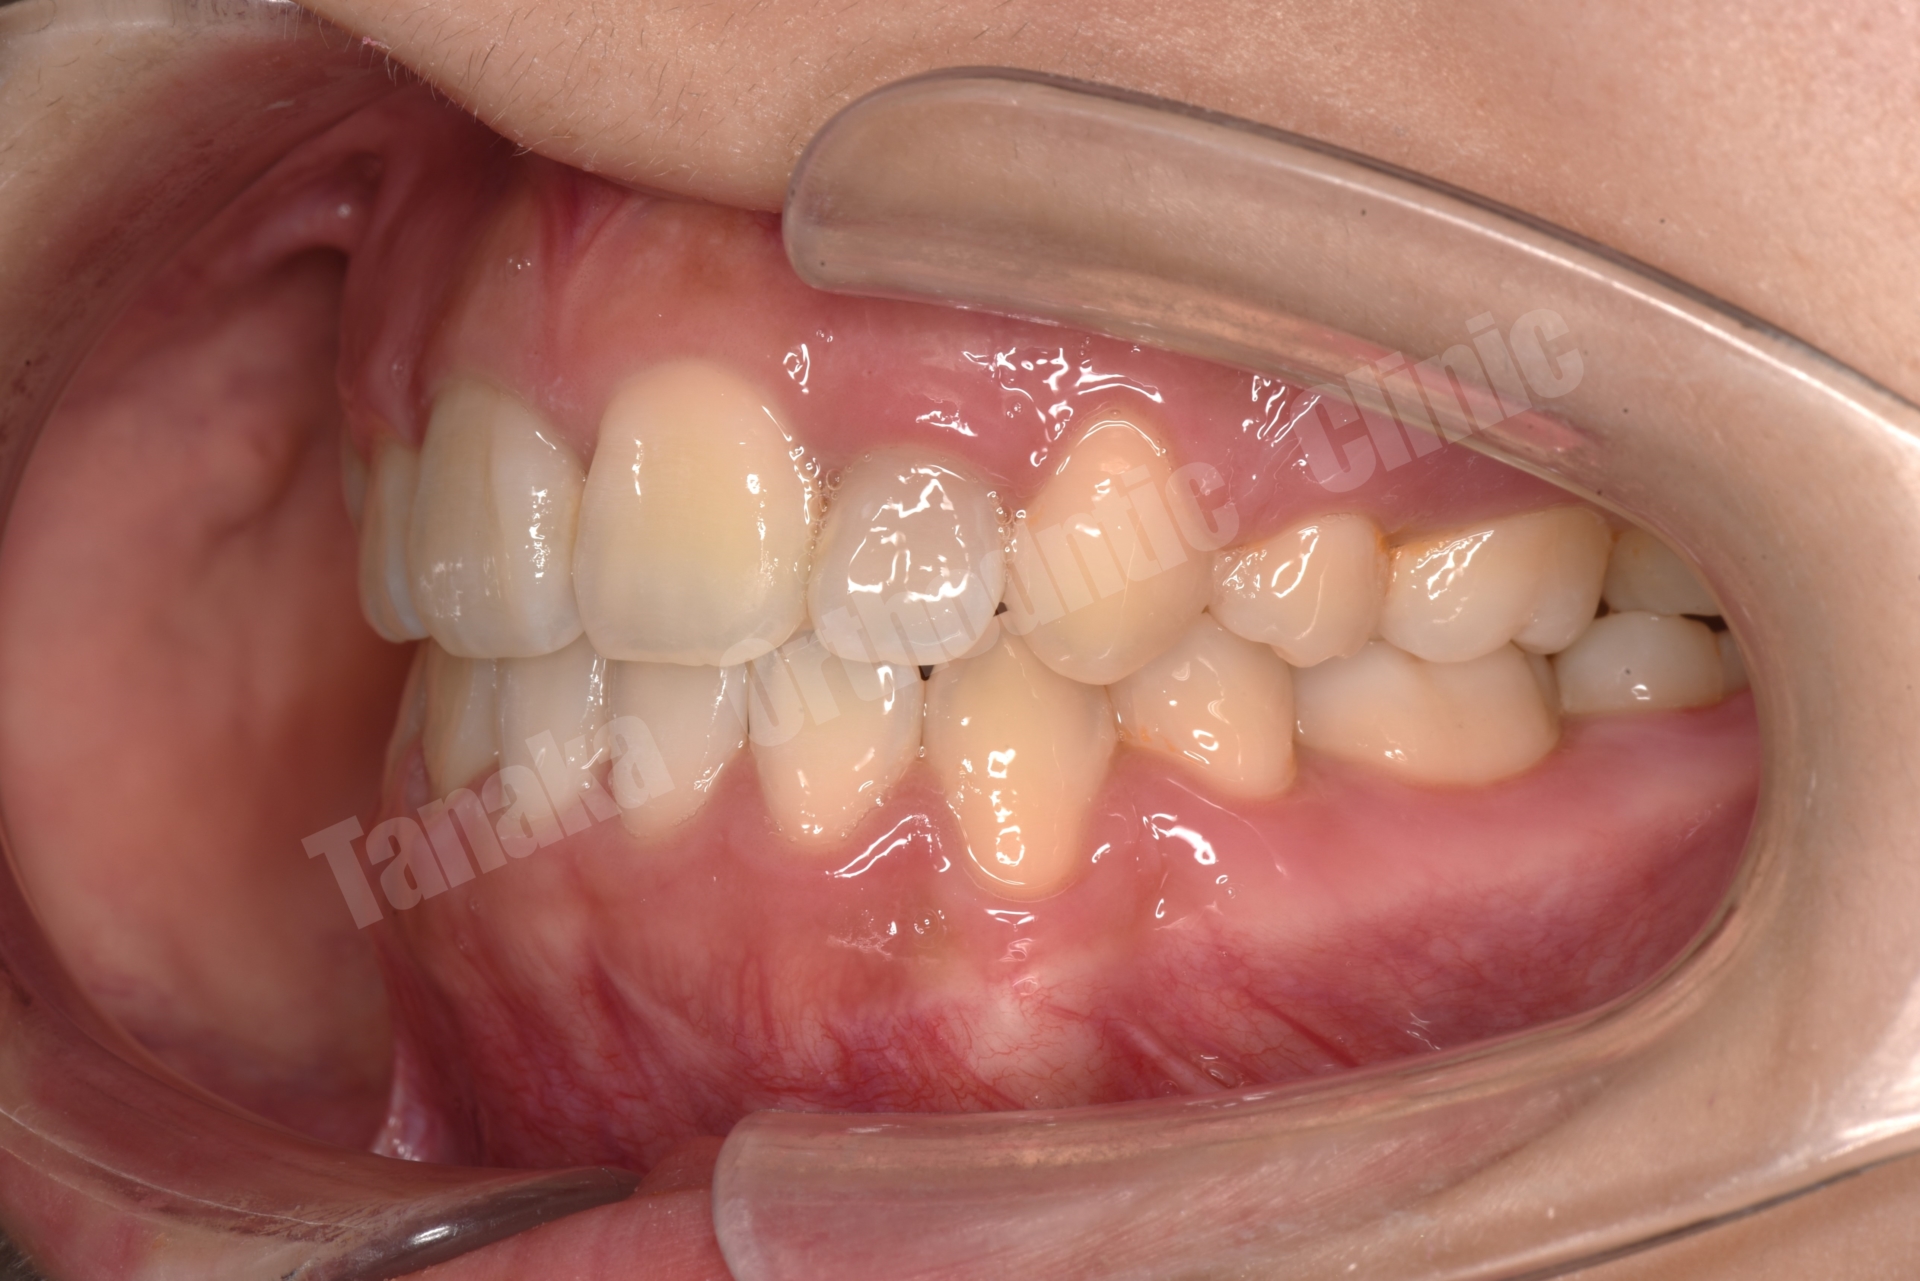

| 主訴 | 上下顎前歯のがたがた、口元が気になる |

| 年齢・性別 | 10代、女性 |

| 治療期間 | 約1年 |

| 抜歯/非抜歯 部位 | 上下4番抜歯 |

| 治療装置 | 唇側マルチブラケット装置 顎間ゴム 矯正用アンカースクリュー |

約1年1か月でデボンド(装置撤去)完了!

最終的には、整った歯並び・自然な口元・清掃性の改善を実現